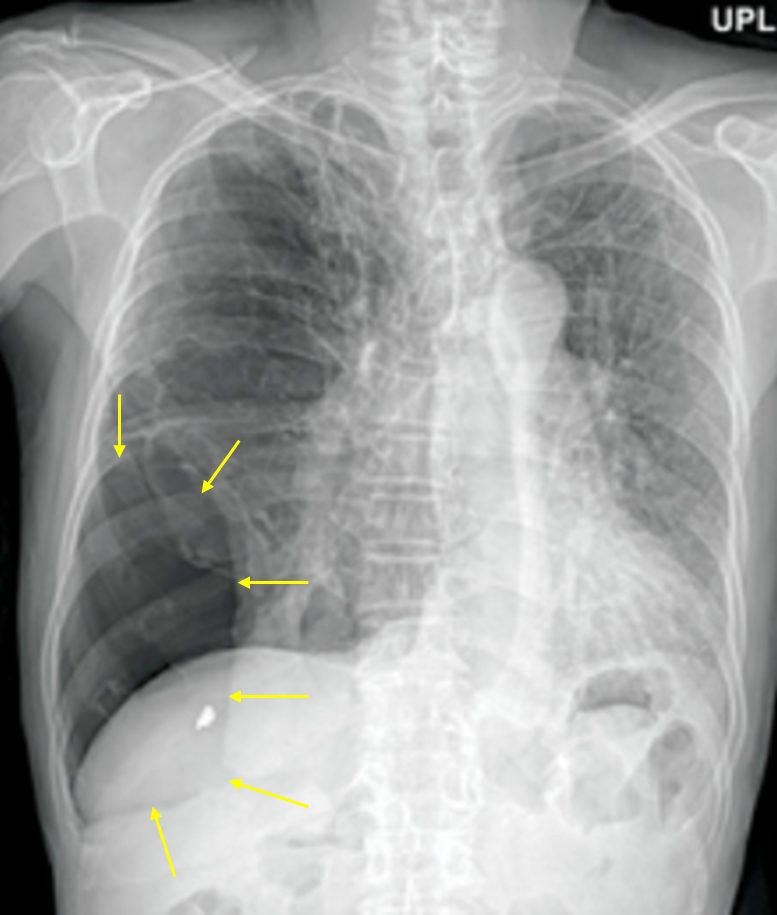

73세 남자가 1일 전부터 가슴이 아프고 숨이 찬다며 병원에 왔다. 50갑·년의 흡연자로 10년 전부터 만성폐쇄폐질환으로 흡입제를 사용 중이라고 한다. 혈압 140/90mmHg, 맥박 110회/분, 호흡 23회/분, 체온 37℃이다. 오른쪽 아랫가슴에서 호흡음은 감소되고 타진에서 가스팽만음이 들린다. 가슴 X선 사진이다. 진단은?

Img | CXR: 우측 폐 하부 pleural line |

• CXR에서 우측 폐에 pleural line과 distal vascular marking의 소실이 보이므로 기흉으로 진단할 수 있다.

• 한편 COPD 병력이 있으므로 이차성 기흉으로 생각할 수 있다. 이차성 기흉은 특히 본 환자처럼 localized된 양상을 보이는 경우가 많다.

• COPD 환자의 경우 큰 공기집(bullae)이 기흉으로 오인되는 사례도 많지만, 본 환자는 급성 흉통, 호흡곤란 등 기흉에 합당한 임상양상을 호소하고 있으므로 기흉으로 보는 것이 더 적절하다. 정확한 감별을 위해서는 CT가 필요하다.